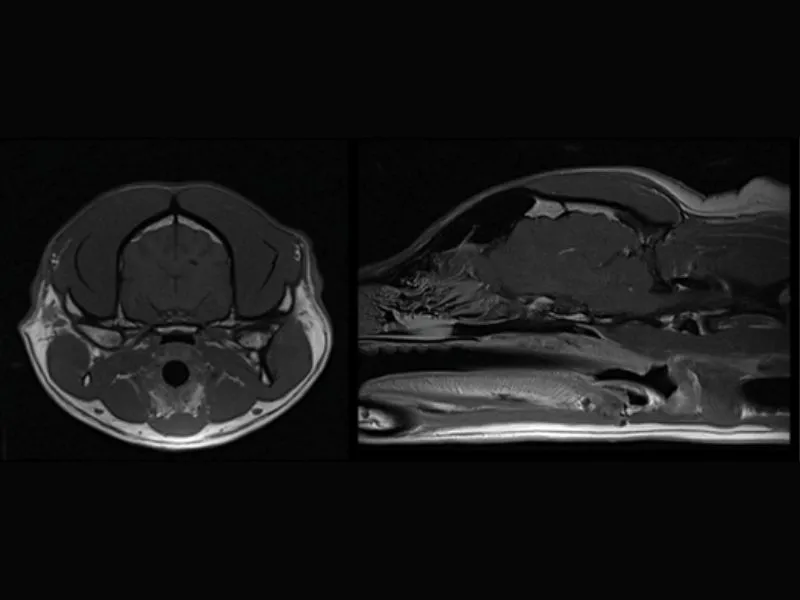

Clinical images

Small animals